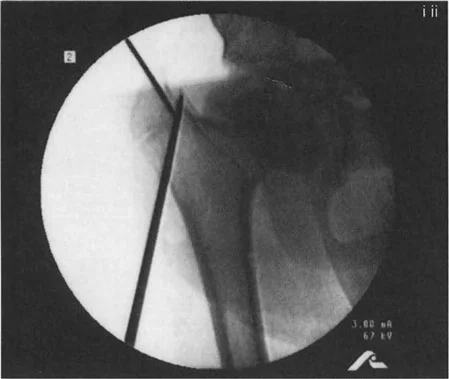

صور توضح حالة كسع الورك مع تضخم المدور الكبير قبل وبعد إجراء قطع عظم واغنر، حيث يتم تصحيح المحاذاة ونقل المدور الكبير.

تسلسل صور بالأشعة السينية يوثق تقنية نقل المدور الكبير بالمنظار، من إدخال سلك التوجيه والقطع إلى التثبيت بالمسامير.